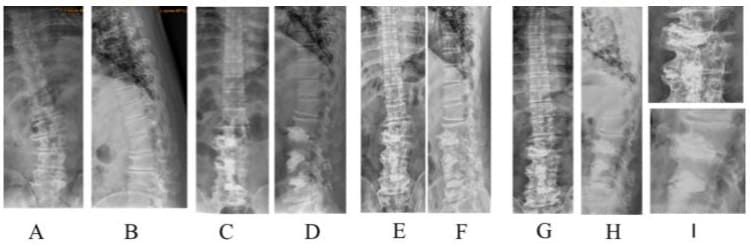

Figure 5: Case demonstration of a 53-year male patient with 26° DLS; A and B: pre-operation; C and D: post-operation 1-month followup; E and F: 78-month follow-up, G, H, and I: 9-year follow-up. He was symptom-free and enjoyed his life as an active farmer.

(Figure 8) The initial correction of scoliosis was 31.6° ± 10.2° vs. 15.1° ± 5.2° (p<0.001) and that of lordosis was 33.8° ± 21.9° vs. 21.7° ± 13.1° (p<0.001). The final correction of scoliosis was 25.5° ± 10.3° vs. 12.6° ± 5.2° (p<0.001), and lordosis was 28.9° ± 24.0° vs. 19.0° ± 13.1° (p=0.02). Significant improvements in lumbar lordosis and Cobb angle were observed in both the groups (Figures 9&10).

Figure 9: A 60-year-old female with degenerative scoliosis (A, B) underwent L2/S1 OIBC. One-month follow-up showed good correction (C, D). The patient remained symptom-free at the final follow-up after six years. (E, F).

Figure 10: A 79-year-old female with degenerative scoliosis 40° and lumbar kyphosis 34° (A, B) underwent PIBC. Immediate postoperative scoliosis was 5° and lumbar lordosis was 13° (C, D). Eighteen months later, the scoliosis was 3° and lumbar lordosis was 5° (E, F). Asymptomatic cement leakage was observed on the ventral side of the L1 vertebral body.